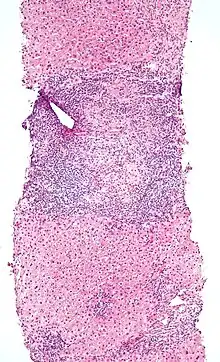

Low-magnification micrograph of PBC, H&E stain

On microscopic examination of liver biopsy specimens, PBC is characterized by chronic, nonsuppurative inflammation, which surrounds and destroys interlobular and septal bile ducts. These histopathologic findings in primary biliary cholangitis include:[32]

- Inflammation of the bile ducts, characterized by intraepithelial lymphocytes

- Periductal epithelioid granulomas.

- Proliferation of bile ductules

- Fibrosis (scarring)